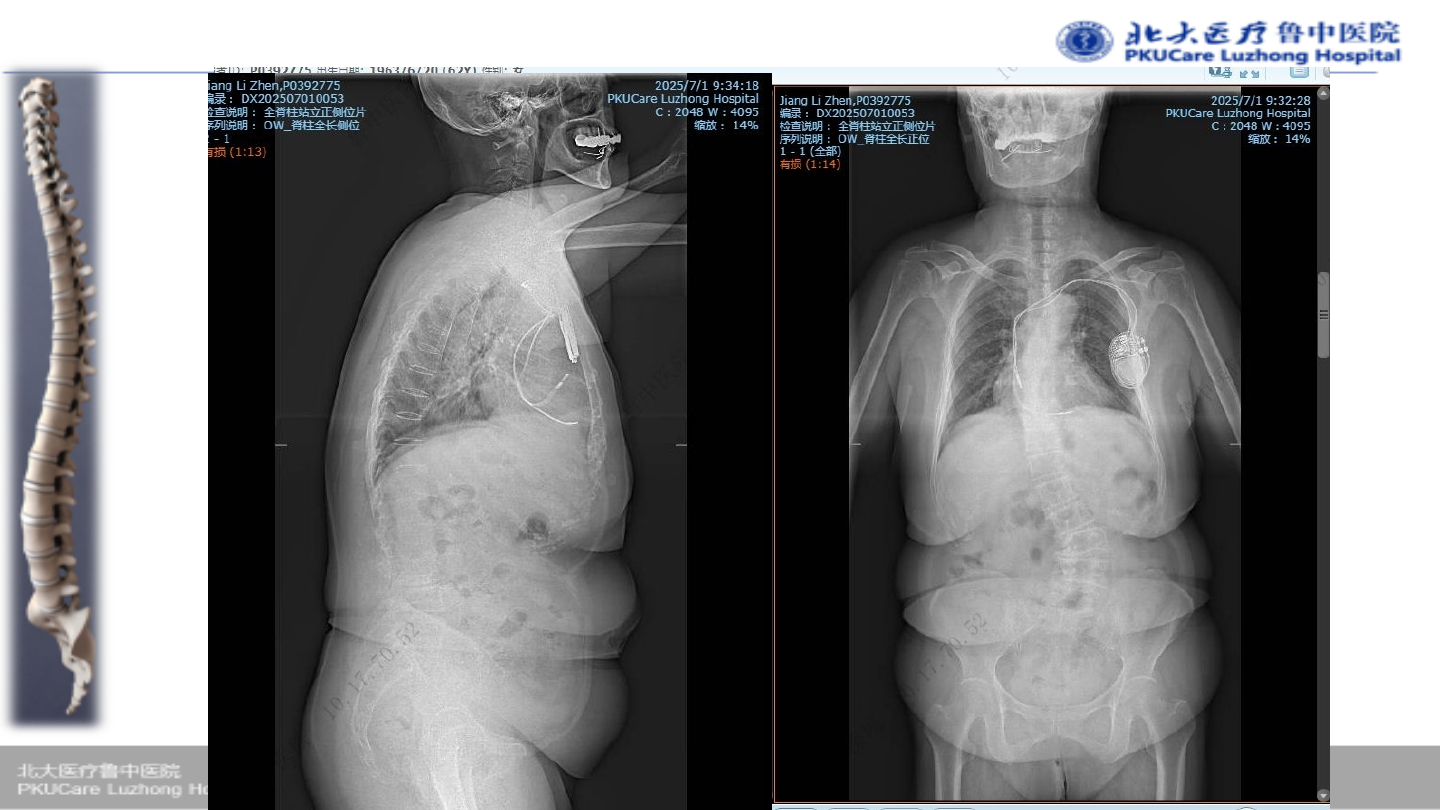

患者:姜某 女性,

67

主诉:

腰疼伴活动受限

2

症状:腰痛,活动后疼痛明显,跛行约

30

.

Oswestry

功能障碍指数(

ODI

):

85%

VAS

7

既往史:心脏起搏器植入史;焦虑症

病例

1

术前腰椎

x-ray